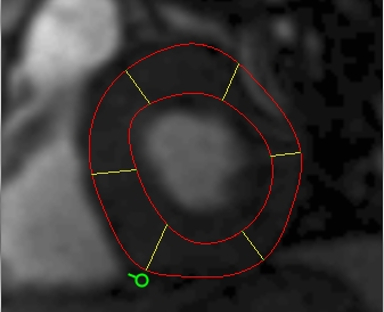

| 10.心臓解析 | 左室心筋のセグメンテーションと心臓解析 | ![]() |

| 自動化された心臓と血管の輪郭曲線のプロパゲーション | ||